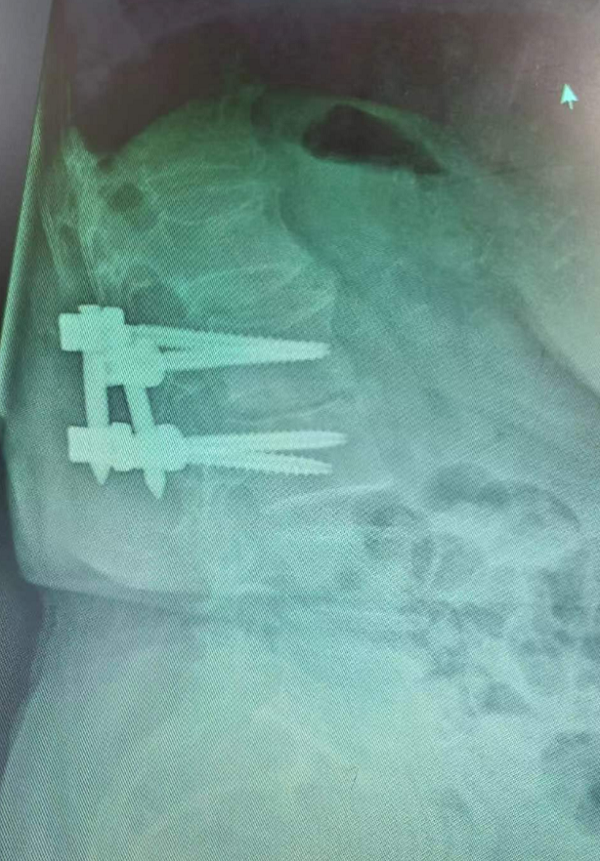

术后经皮螺钉内固定影像学检查

骨科(脊柱外科)医师团队详细讨论后为王奶奶制定了治疗方案,经术前积极抗结核治疗后,为患者实施手术,术中仅用5个小切口便解决了患者的大问题,术中出血少,时间短,术后患者各项指标正常,顺利返回病房。术后两周,患者满意出院,患者及家属对治疗效果非常满意。